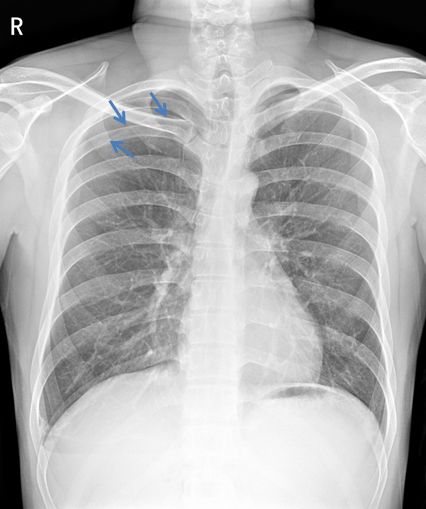

病例1

病例1患者的X线胸片

左上肺肺野可见肺叶压缩带边缘,肺叶压缩约30%(灰色区域)。左下肺野可见液-气平面,约与第5前肋相平(蓝色虚线),肺门影不浓。心影及纵隔向对侧轻度移位。

侧位片可见左侧肋膈角变钝,少量胸腔积液